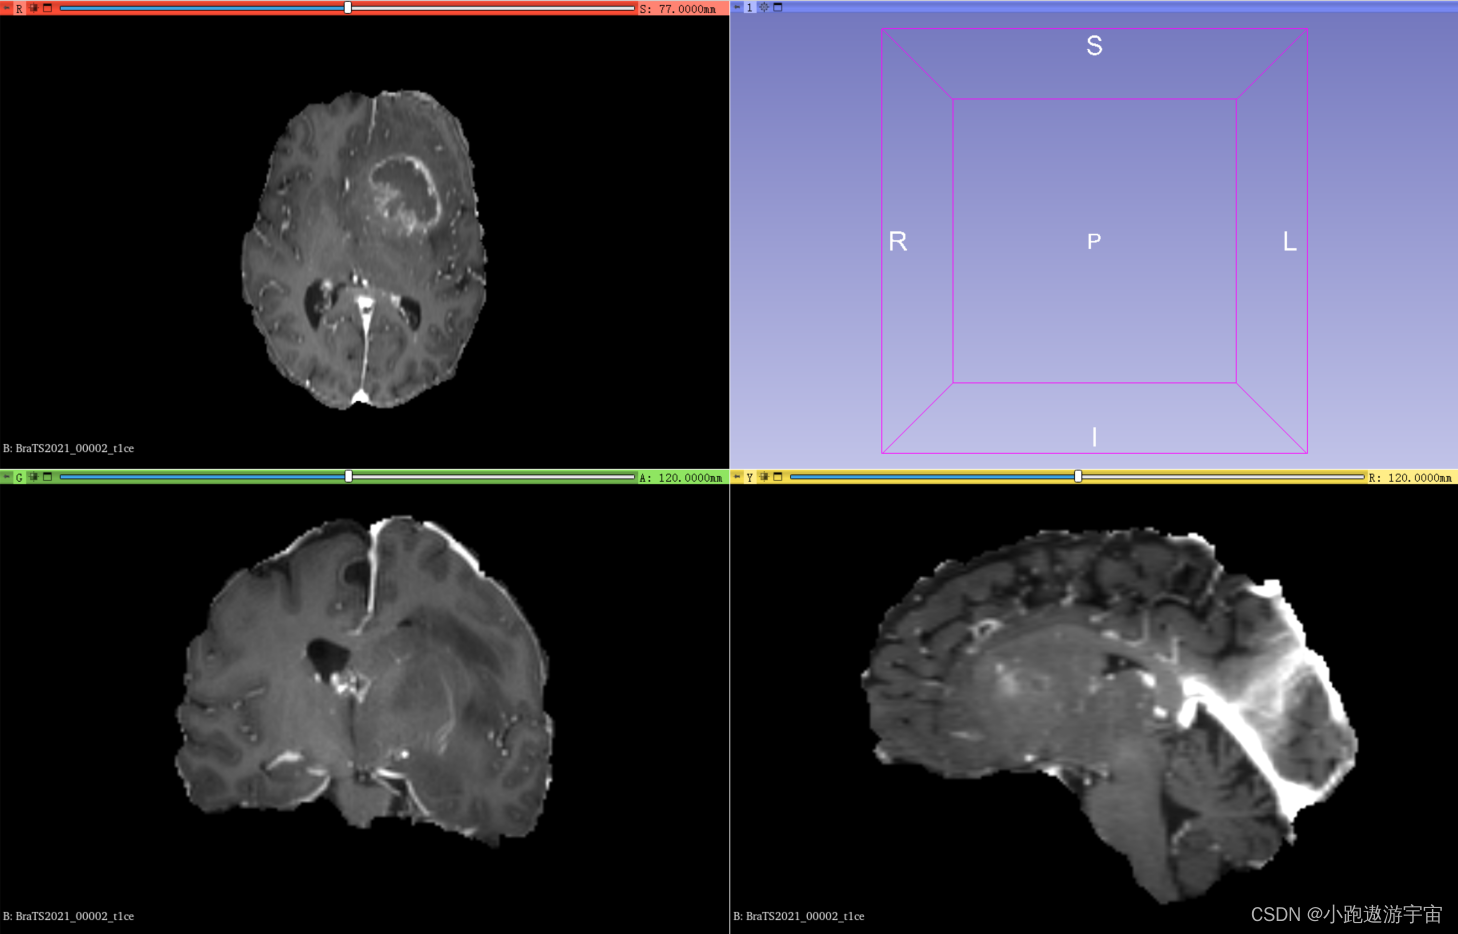

T1对比增强成像(T1-weighted imaging with contrast enhancement, T1CE):这种成像方式是在T1序列的基础上加入了造影剂,能够帮助检测到肿瘤和炎症等病变。T1CE序列主要用于显示肿瘤和炎症等异常组织。

BraTS2021_00002_t1ce.nii.gz